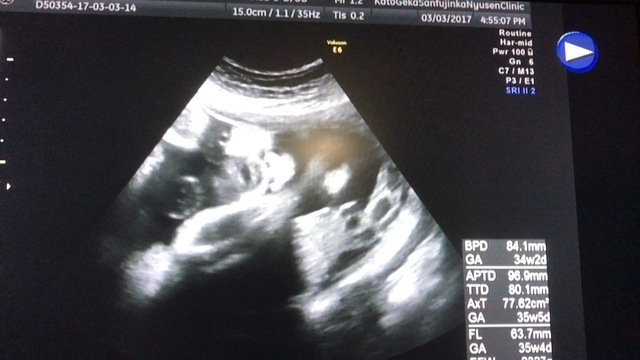

34週2日(34w2d・女の子)|みのりん さん(28歳)

エコー写真撮影時のエピソード:

それまでは、人のような形で写っていましたが、初めてはっきりと顔と手が見えて感動しました。 しっかりおなかの中で大きくなってくれてる!しかも、かわいい!って目がハートになりました。出張で離れて暮らしていた主人にも画像を送り、喜び合いました。